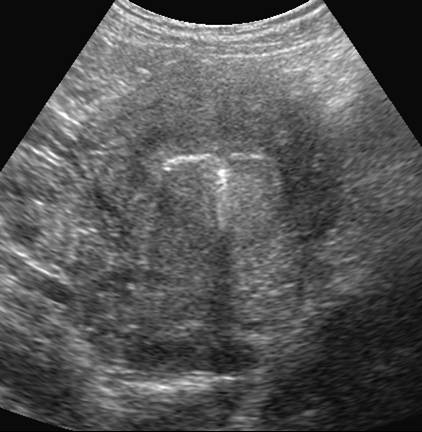

DIU en place, coupe frontale